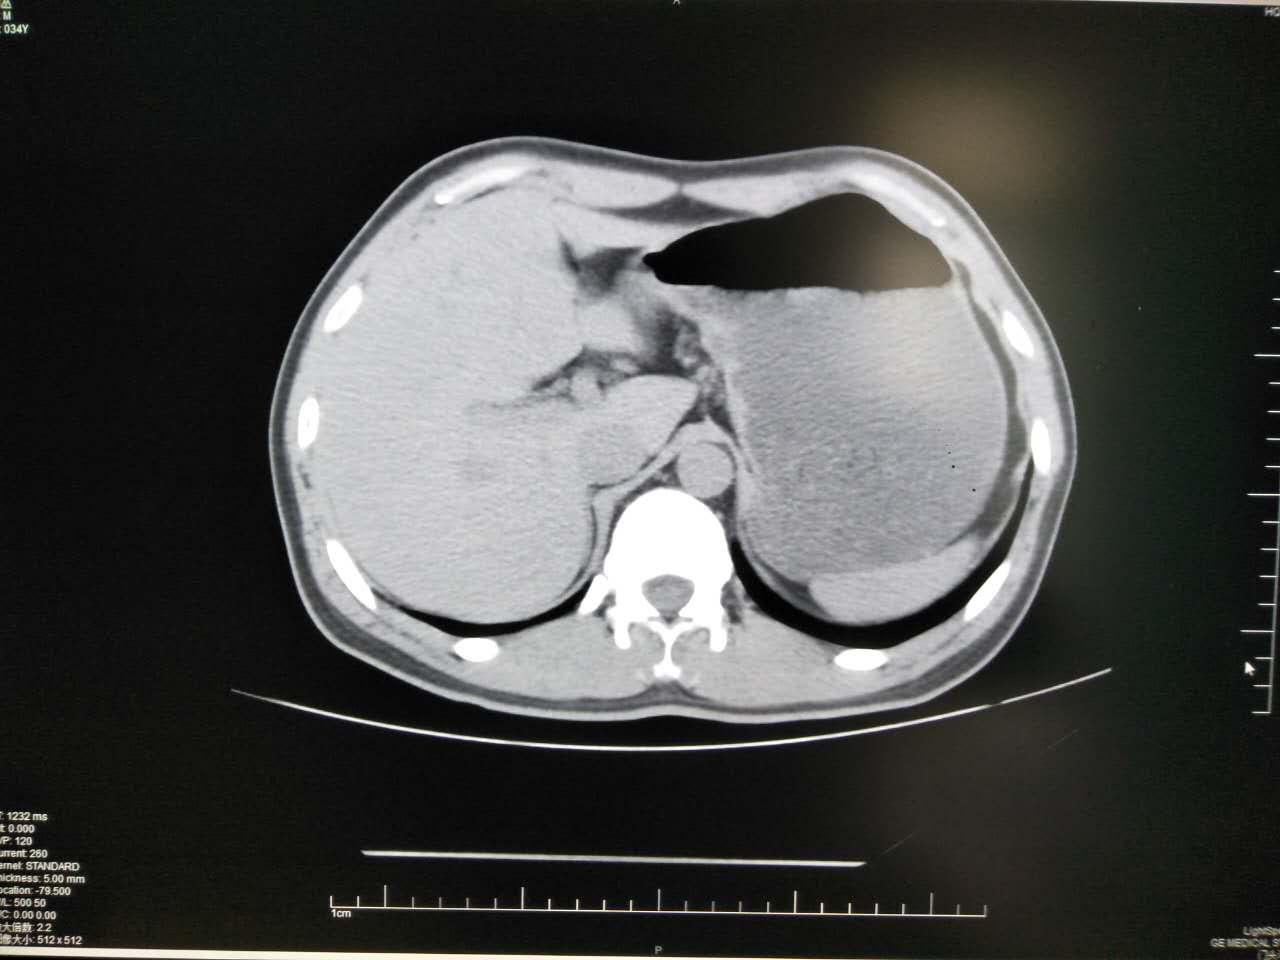

胃肠道CT 检查如要获得高质量的图像,肠道准备非常重要。如果小肠内有食物残渣, 就会影响肠腔的充盈与扩张,对于胃肠壁上较浅的病变难以显示。以下两例就是胃肠道未作准备,内容物较多,影响对比度,从而影响检查效果。

以下几例是胃肠道对比度较好的例子,可以清晰显示胃肠壁有无病变。